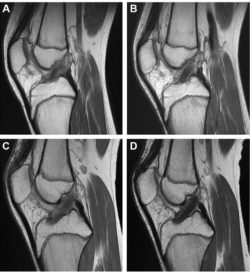

(A) Sagittal MRI 6 months after ACLR with HTA. (B) Sagittal MRI 12 months after ACLR with HTA (same patient as in panel A). (C) Sagittal MRI 6 months after ACLR with QTA. (D) Sagittal MRI 12 months after ACLR with QTA (same patient as in panel C). ACLR, anterior cruciate ligament reconstruction; HTA, hamstring tendon autograft; MRI, magnetic resonance imaging; QTA, quadriceps tendon autograft.

Main Results: Age, sex, and type of surgery were not associated with any differences in SIR. There was no significant difference in SIR between groups on the 6-month MRI. However, the SIR of the QTA group was significantly less than in the HTA group on the 12-month MRI. Within the HTA group, there was no significant difference in SIR at either MRI time point. In the QTA group, there was a significant decrease in SIR between the 6-month and 12-month postoperative MRI.

Conclusion: These findings suggest improved graft maturation, remodeling, and structural integrity of the QTA compared with the HTA between 6 and 12 months postoperatively. This provides evidence that, at 1 year postoperatively, QTA may have a superior rate of incorporation and synovialization as compared with the HTA.